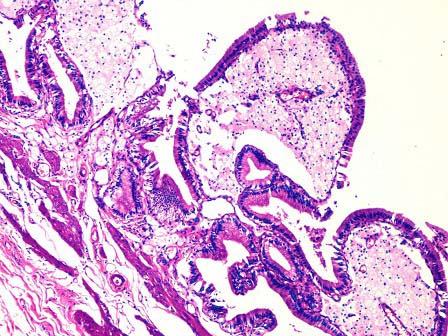

问题 某患者,右上腹痛1小时入院,B超示胆囊肿大,内壁毛糙。手术切除胆囊送检。巨检胆囊7cm×5cm×3cm,腔内含泥沙样结石,内壁粗糙,壁厚0.3cm。镜下观如图,诊断为 ( )

选项 A.慢性胆囊炎 B.慢性胆囊炎并胆固醇息肉形成 C.胆囊癌 D.慢性胆囊炎急性发作 E.以上均不是

答案 B